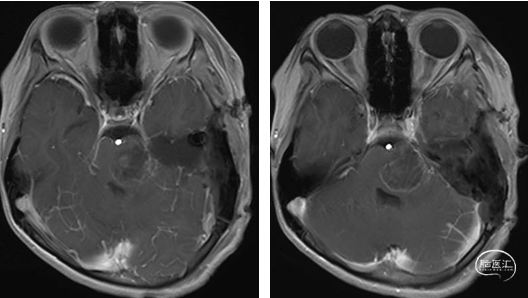

术前MRI

术后MRI